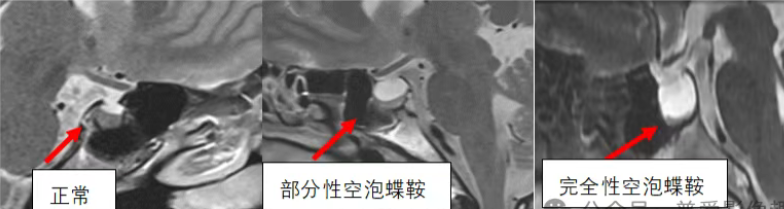

MRI是评估空泡蝶鞍的首选影像学检查方法。根据影像表现,可分为完全性空泡蝶鞍与部分性空泡蝶鞍。完全性空蝶鞍通常指脑脊液填充蝶鞍范围超过50%,且垂体厚度≤2mm;部分性空泡蝶鞍则指脑脊液填充不足50%,垂体厚度一般在3mm至7mm之间。